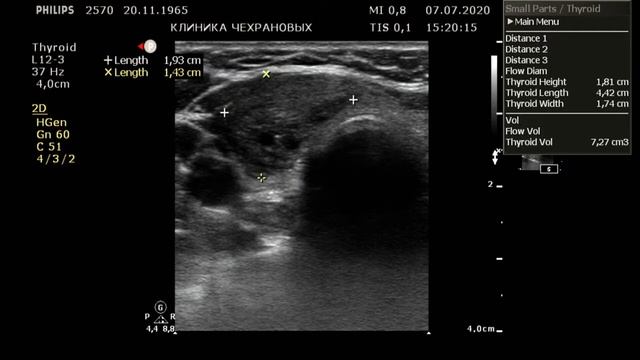

Узи tirads 3

Узи tirads 3 100 фотографий